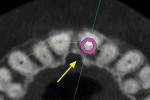

Recent software developments allow for a simulated implant to be visualized in the axial view in close proximity to the incisal canal (yellow arrow), and the periodontal ligament space of the adjacent tooth roots (Figure 5). Using advanced software features and the process of segmentation, the existing tooth root can be virtually extracted, leaving the remaining alveolus to be inspected (Figure 6). The use of “selective transparency” provides the necessary information regarding positioning the implant and avoiding the adjacent tooth roots (Figure 7). The proposed implant with an abutment projection can then be positioned to emerge through the desired restorative result, linking the implant to the envelope of the tooth.